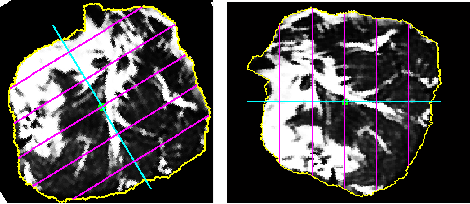

2.6 Fragmenting ES muscles

The next step is to quantify fat in fragmented regions of the erector spinae (ES) muscles. The segmented muscles could be sub-divided into many regions. We have subdivided the segmented muscles into six regions with reference to the centre of the spinal column, as shown in Figure 8 and Figure 9. The use of six fragments was based solely on visual observation by a clinical biomechanist and clearly needs further research. Generally, the segmented muscle region is irregularly shaped. The boundary points are extracted and used to sub-divide the region into smaller segments. After obtaining the various segments, the fat content percentage in each segment is calculated.

The following steps are used to subdivide the segmented region and to perform the computations:

Step 1: The centre of the spinal column is automatically detected for a given input image.

Step 2: A radial line from the centre of the spinal column , which passes through the centroid of the segmented muscle region and that bisects the ES muscles is plotted, as shown in Figure 7.

Step 3: Considering the radial line as vector and a horizontal line through the centre of the spinal column as vector , the angle between the vectors and is calculated.

Step 4: The angle is used to identify, whether the segmented muscle region lies either on the right side or the left side of the spinal column. If the angle is less than the segmented muscle region is considered to be on the right side and it is rotated by angle in the counter-clockwise direction as shown in Figure 8, else the segmented muscle region is considered to be on the left side and it is rotated by an angle in the clockwise direction as shown in Figure 9.

Step 5: From the segmented muscle region, the contour as a set of points, is extracted. Subsequently the vectors and pertaining to the contour points of the X-coordinates and Y-Coordinates, respectively, were extracted.

Step 6: The maximum and minimum values of and are found, which gives the extremities of the irregular shaped segmented muscle region.

Step 7: The length of the segmented region, which is the difference between the maxima and minima of is calculated. Further, the length is used to sub-divide the segmented muscle region.

Step 8: To have six sub-divisions, five equidistant vertical lines are plotted over the segmented lumbar muscle region at regular intervals from the minima of . These vertical lines are plotted from minima of to maxima of so that every line touches the contours of the segmented muscle region as shown in Figure 8 and Figure 9.

Step 9: Considering all seven hyperplanes, one each at the minima and maxima of and one at each of the five vertical lines, the fat content in six smaller segments are calculated.

Step 10: The fat content in every smaller segment is calculated by subjecting every pixel inside the region to the sigmoid function with the pre-selected threshold and softness level.